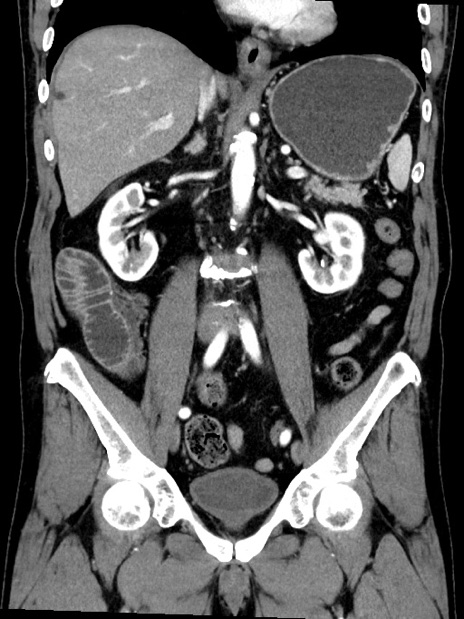

症例35(冠状断像)

【症例】70歳代 男性

【主訴】腹部膨満、嘔吐

【現病歴】昨日より腹部膨満感出現。本日増悪し、仙痛出現。嘔吐あり、受診。

【既往歴】糖尿病、胆摘後

【身体所見】BP 149/80mmHg、HR 74/min、BT 35.9℃、腹部:膨満、軟、圧痛なし。腸雑音減弱あり。上腹部正中切開瘢痕あり。

【データ】WBC 13500、CRP 1.72